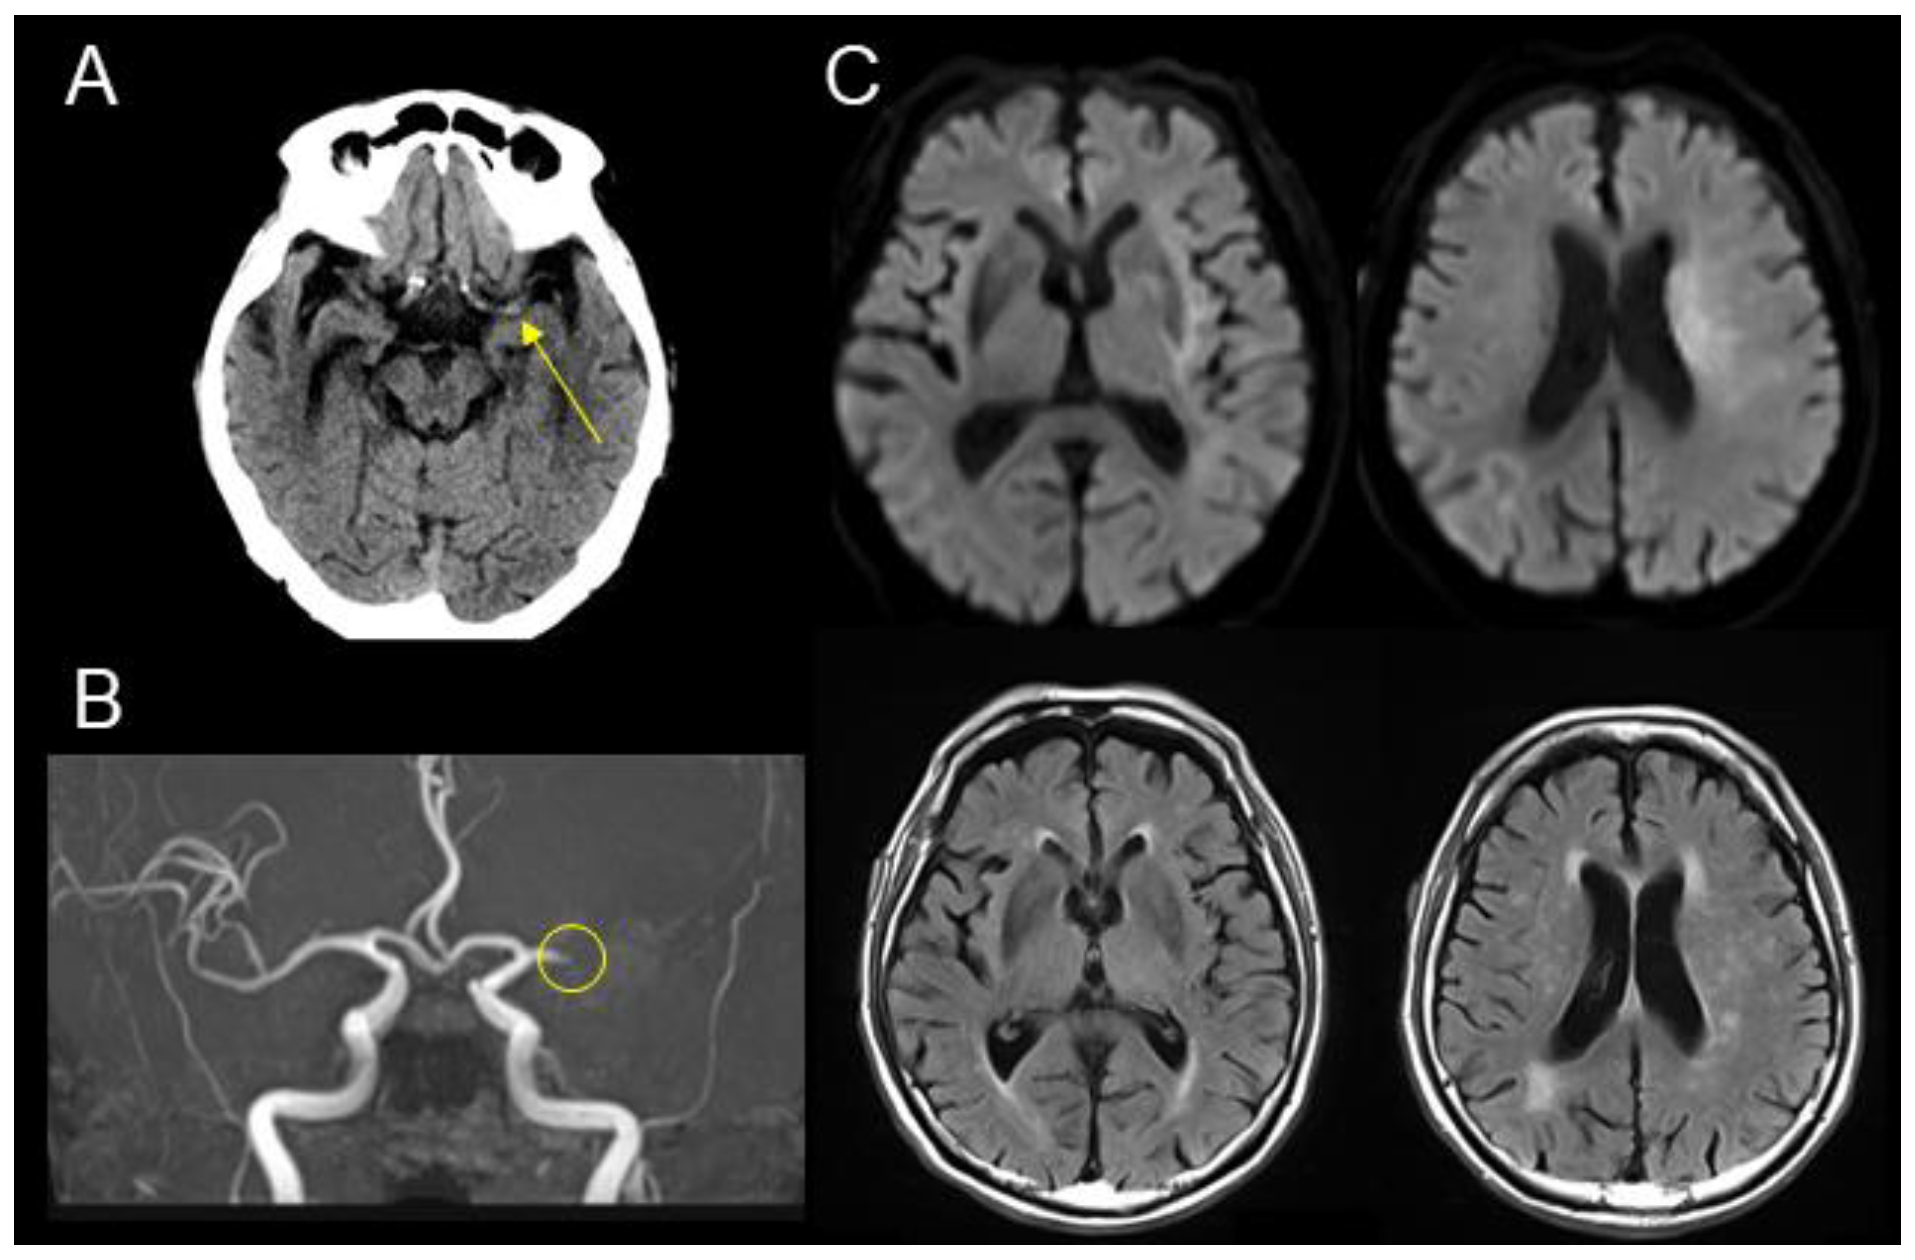

Diffusion MRI Fiber Tractography and Benzodiazepine SPECT Imaging for Assessing Neural Damage to the Language Centers in an Elderly Patient after Successful Reperfusion Therapy

2. Case Presentation